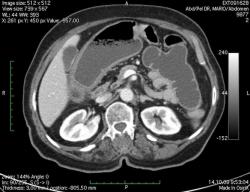

КТ брюшной полости. Женщина 73 года с жалобами на запоры.

Пациентка женщина 73 года. Предъявляет жалобы на запоры, спастические боли в брюшной полости.

ИзображениеЦиркулярное сужение в поперечной ободочной кишке. Ни это ли причина проблемм?

Новообразование в среднем отделе поперечной ободочной кишки с циркулярным сужением просвета и хронической механической толстокишечной непроходимостью. Признаков метастазирования в данной анатомической области не обнаружено. Пациент безусловно нуждается в хирургическом лечении.

Я не занимаюсь КТ, но сам характер сужения толстой кишки как-то вызывает сомнения, ракового ли он характера? Сужение то циркулярное, но больно уж ровненькое и нет признаков инфильтрации вокруг (хотя рак, конечно может иметь и такой вид). Ну, думаю dr.Mario со временем откроет карты и будет дана гистология.

Циркулярная стенозирующая опухоль (аденокарцнома) толстого кишечника; с типичной КТ презентацией и признаками обструкции. Пациентка была оперирована на второй день после КТ.